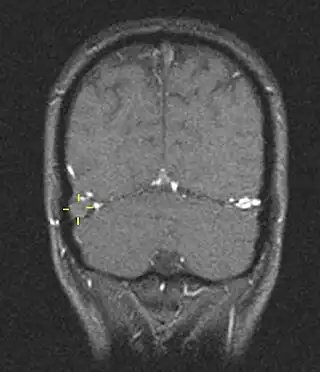

La trombosis del seno venoso cerebral (CVST) es la presencia de trombosis (coágulo sanguíneo) en el seno venoso dural, que recibe sangre de venas externas e internas del cerebro. Los síntomas de esta enfermedad pueden incluir dolor de cabeza, visión anormal, cualquiera de los síntomas de un accidente cerebrovascular (debilitamiento de los músculos de la cara y extremidades de una mitad del cuerpo) e infartos. El diagnóstico se realiza normalmente por tomografía axial computarizada (CT/CAT scan) o resonancia magnética (MRI) empleando el contraste radiológico para demostrar obstrucción de los senos venosos por trombos.[1]

Hay varias formas de neuroescaneo que pueden determinar la presencia de la trombosis del seno venoso cerebral. Los edemas cerebrales e infartos venosos pueden hacerse visibles en cualquier modalidad, pero para la detección del trombo sí, el tipo de escaneo más usado comúnmente son la tomografía axial computarizada (CT) y la resonancia magnética (MRI). Ambas usan varios medios de radiocontraste para elaborar un venograma y visualizar las venas en torno al cerebro.[1]

La tomografía axial computarizada tiene una capacidad de detección que para algunos expertos supera la de la resonancia magnética. Esta prueba se basa en la inserción, a través de una inyección en la vena (normalmente en el brazo), de una sustancia radiopaca. Tras un tiempo, el que tarda el torrente sanguíneo en llevar la sustancia al cerebro, el escaneo se realiza. La sensibilidad de este test es de 75-100% (detecta de 75 a 100% de todos los coágulos presentes), y una especificidad de 81-100% (sería incorrectamente positivo en un 0-19%).[6]

La resonancia magnética venosa emplea los mismos principios, pero la modalidad de escaneo usada es la resonancia magnética. La MRI tiene la ventaja de ser mejor a la hora de detectar peligro para el cerebro como resultado del incremento de la presión en las venas obstruidas. No obstante, este mecanismo no se encuentra disponible en muchos hospitales y su interpretación puede resultar dificultosa.[6]